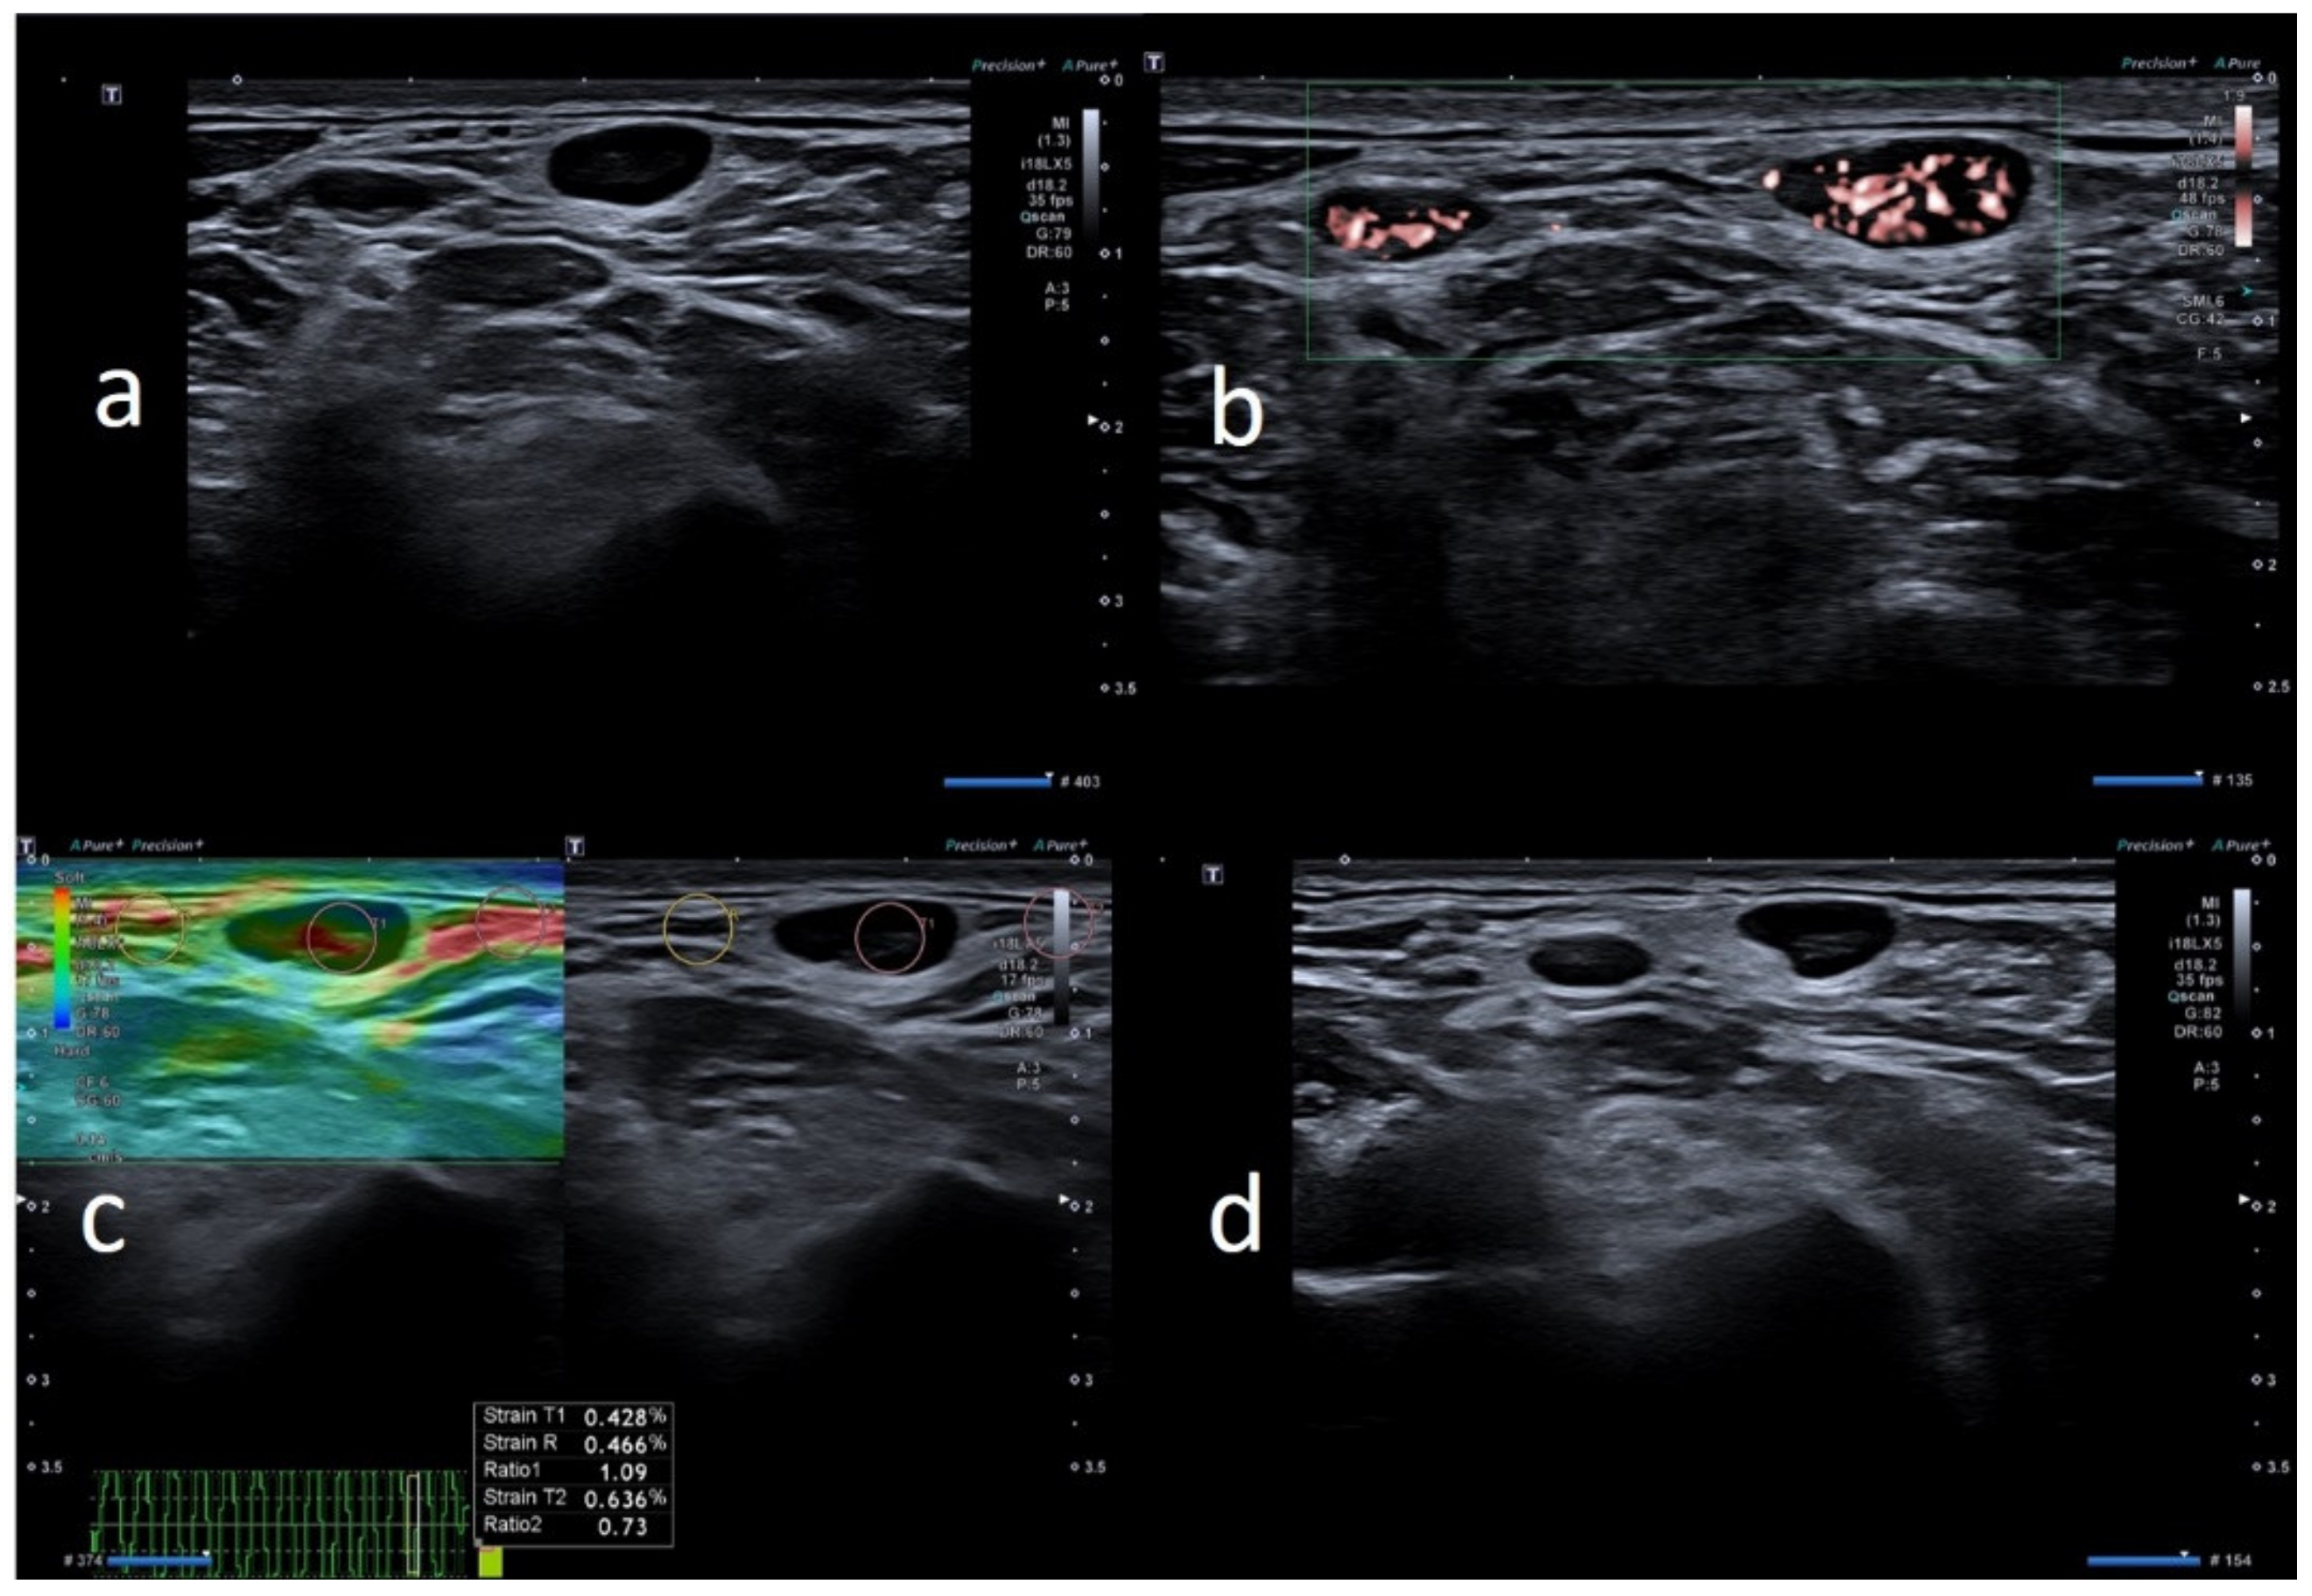

| W | 25 | Pfizer | Axillary ipsilateral to vaccine injection | Three days after first dose of vaccine, axillary swelling and pain present. Also hypomobility ipsilateral arm | None | 6 | Variable: from 0.7 cm to 2.8 cm | Ovular | Prev. no hilum evidence | Prevalent hard pattern | Central and peripheral vascular signals | Normalized to 60 days |

| W | 28 | Astazeneca | Supraclavicular ipsilateral to vaccine injection | Two days after first dose vaccine, supraclavicular swelling and pain present | None | 3 | Variable: from 0.6 to 1.5 cm | Ovular | No evidence hilum | Prevalent hard pattern | Central and peripheral vascular signals | Normalized to 45 days |

| M | 39 | Astazeneca | Supraclavicular ipsilateral to vaccine injection | Four days after first dose vaccine, supraclavicular swelling and pain present | None | 1 | Subcentimetric size | Round | No evidence hilum | Prevalent hard pattern | Central and peripheral vascular signals | Normalized to 30 days |

| W | 26 | Astazeneca | Supraclavicular ipsilateral to vaccine injection | 2 days after the first dose vaccine, axillary swelling and pain present | None | 5 | Subcentimetric size | Ovular | No hilum evidence | Prevalent hard pattern | Central and peripheral vascular signals | Normalized to 45 days |